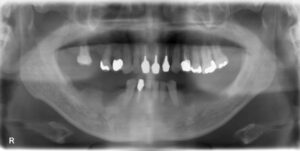

上顎臼歯1本欠損症例

BEFORE AFTER 21歳女性/上顎1本欠損/インプラント埋込手術 【治療内容】 左上第一大臼歯の炎症が強く、保存…